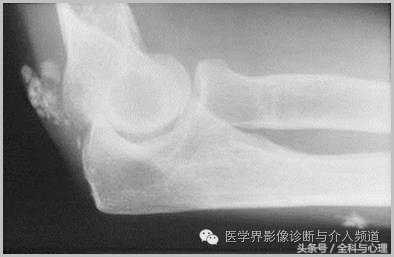

五、滑膜软骨瘤病

1°少见,病灶数量多,大小均匀,相邻关节正常。

2°多见,病灶数量少,大小不一,多伴有退行性骨关节病。

滑膜骨软骨瘤病 1°

滑膜骨软骨瘤病 2°

滑膜骨软骨瘤病